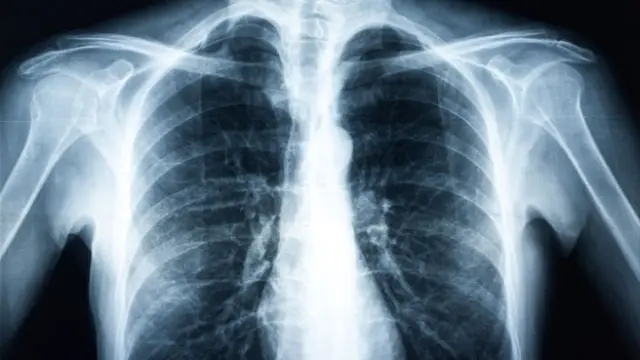

Buena parte de la población de los países en vías de desarrollo padece asma, fibrosis quística y otras enfermedades pulmonares crónicas. Sin embargo, a causa de las condiciones deficitarias de la asistencia sanitaria, estos pacientes no cuentan con un diagnóstico adecuado ni con un tratamiento para combatir la patología.

La solución que han propuesto los científicos de la Universidad de Washington tiene un gran potencial para ayudar a todas estas personas. La plataforma se llama SpiroCall y puede medir con precisión la función pulmonar de cualquier persona a través de un teléfono convencional, sin necesidad de que sea un smartphone.

Para utilizar esta herramienta, lo único que tiene que hacer el paciente es respirar profundamente y exhalar tan fuerte y rápido como le sea posible en el auricular de su terminal, hasta que no pueda exhalar más. El micrófono del teléfono del receptor tiene la capacidad de detectar el sonido y la presión de la exhalación, datos que después envía a un servidor central, que utiliza algoritmos de aprendizaje automático para convertir la información en medidas estándar de la función pulmonar.

Los resultados que proporciona la herramienta se sitúan a un 6,2% de los que ofrece un espirómetro clínico, de manera que la plataforma cumple con las normas de la comunidad médica en términos de exactitud.